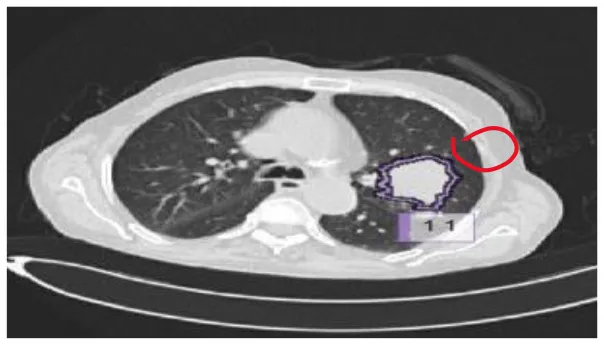

The results were enhanced by using the ROI segmentation method. It seems that it has the capacity to address the problem of the model's inaccurate positioning of labels. As a consequence, following the recommended methodology may lead to decreased losses. Furthermore, it was shown that the training session continued to slow down. The lesson is enhanced in its effectiveness as shown in Figure 8. It is advisable to apply the same treatment to both one-dimensional and two-dimensional data. The objective of this strategy is to eliminate any errors in labeling in both directions. Over time, there was a gradual reduction in the size of each point. Engaging in conversations with individuals helps achieve both objectives.

Figure 8

Prior to and during the segmentation procedure, the ground-truth forecast was used in each of these instances.

If the dataset is insufficient, it may be necessary to round up more labels. Overall, there were 159 cancerous tumors, and the standard deviation of the Dice coefficient was 0.2. Although its model had a low mFPI, the DL-based model was successful in detecting lung tumors from chest X-rays, the results are shown in Figure 8. The evaluations of the proposed models are presented in Table 8.